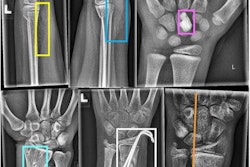

Several factors contribute to underdiagnosis following imaging, including the failure of radiologists to consistently review spinal components of imaging, lack of awareness of the importance of early diagnosis of VFFs and use of ambiguous reporting terminology (e.g., "loss of height" or "wedging"), immature or underdeveloped departmental RIS and alert processes inhibiting rapid dissemination of reports, and inadequate onward referral systems (in particular fracture liaison services), they wrote.

- Implement a policy for standardized use of terminology for VFFs -- using the term "vertebral fracture."

- Consider the use of standard phrases or short codes to create actionable reports or alerts to referrers.